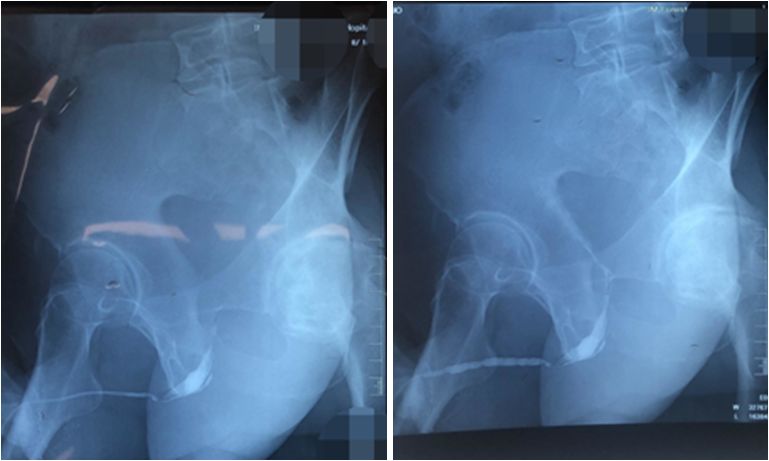

LS累及尿道常起始于尿道外口,长期的病变会导致尿道粘膜及尿道海绵体损害引起排尿梗阻症状。尿道镜下检查发现病变累及的尿道粘膜呈苍白色和绒毛状,偶尔可见尿道内裂隙及溃疡。研究发现LS病变侵犯常终止于近段的球部尿道,没有侵犯前列腺部尿道的报道。临床判断有LS尿道累及的病例,必须经过尿道镜检和逆行尿道造影明确病变段尿道位置等情况,比较典型的尿道造影检查可见病变段尿道粘膜毛糙如锯齿样改变。

病例图片,来源:上海六院